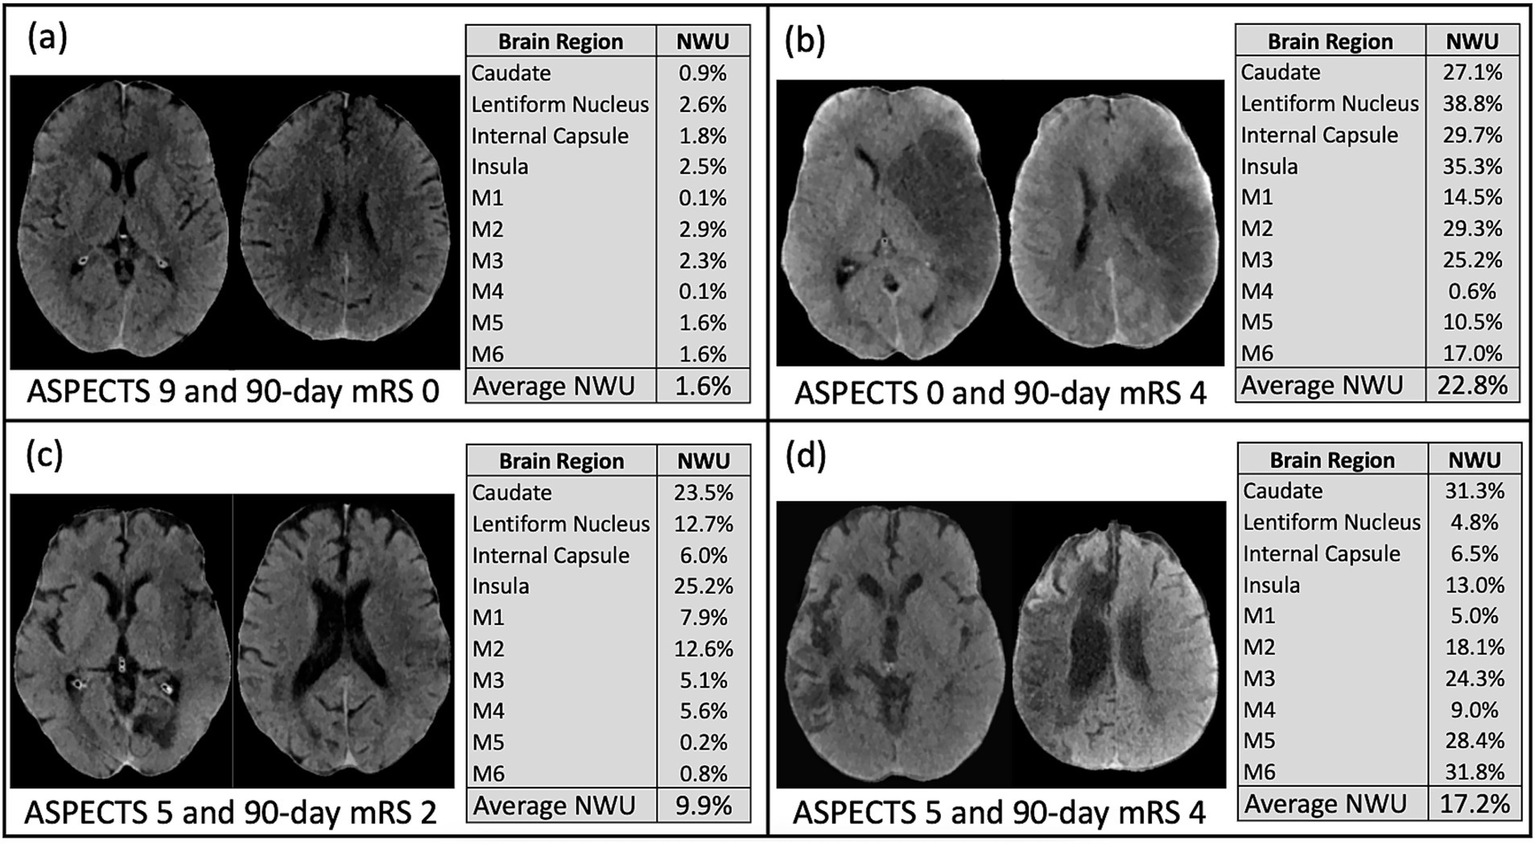

When examining the association between individual brain regions and specific neurologic deficits, logistic regression showed that most of the brain regions showed consistently significant predictive power for the precise deficits except for the caudate and M4 region (see Figure 3 and Supplemental Figure 2). Particular deficits were not isolated to certain brain regions, but rather NWU in almost any region showed significant association to each precise outcome. Lastly, four case examples are shown in Figure 4 to demonstrate some common clinical scenarios and the resulting ASPECTS and NWU findings.

Figure 4

These four examples from the study cohort demonstrate common clinical scenarios. (a) Subject with ASPECTS 9, average NWU 1.6%, and 90-day mRS 0; (b) Subject with ASPECTS 0, average NWU 22.8%, and 90-day mRS 4; (c) Subject with ASPECTS 5, average NWU 9.9%, and 90-day mRS 2; (d) Subject with ASPECTS 5, average NWU 17.2%, and 90-day mRS 4.